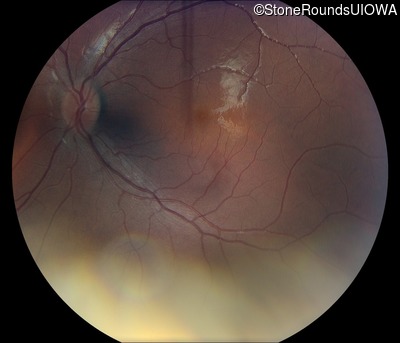

Fundus Photography - Right - 20/50 -1

Exemplar